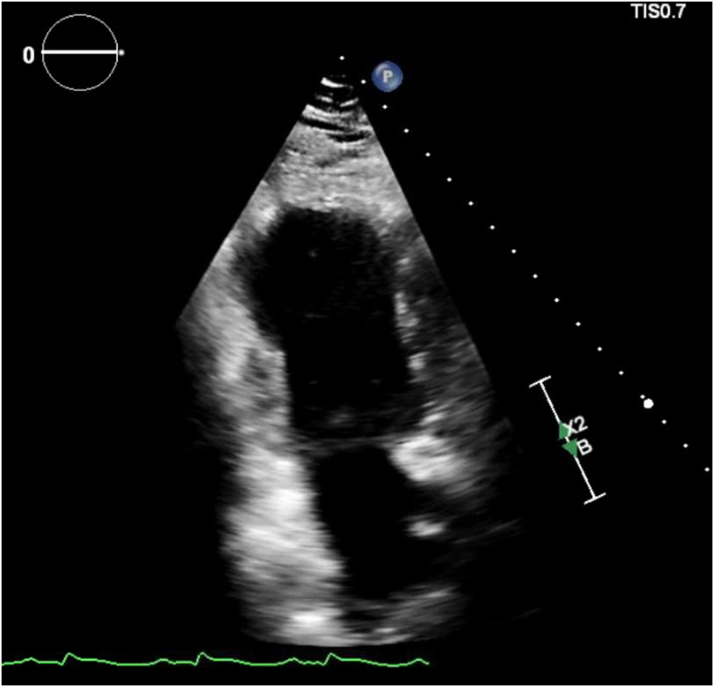

Figure 2.

Echocardiogram Showing Apical Ballooning of the Left Ventricle

The coronary angiogram did not show any obstructive coronary lesions, and right heart catheterization revealed an elevated pulmonary capillary wedge pressure of 30 mm Hg, a cardiac index of 1.4 L/min/m2, and an elevated right atrial pressure of 15 mm Hg, consistent with new heart failure and cardiogenic shock of nonischemic etiology. The echocardiogram showed a left ventricular ejection fraction (LVEF) of 15% to 20%, with mid to apical wall hypokinesis (Figure 2, Video 1).

Trans-thoracic electrocardiogram showing severe mid-to-apical hypokinesis and apical ballooning of the left ventricle.